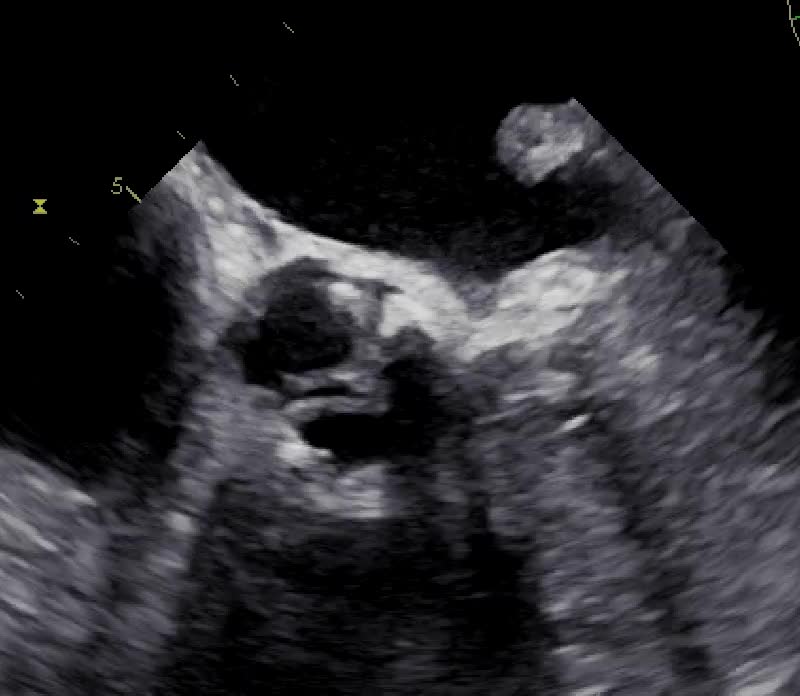

Insufficienza tricuspidale